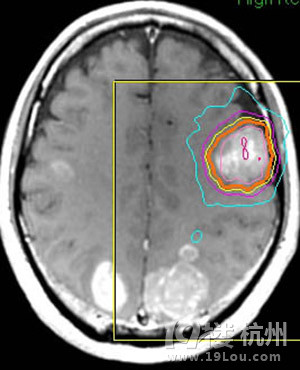

颅内多发转移瘤射波刀怎么治-网上问医-杭州1

300x379 - 32KB - JPEG

300x370 - 31KB - JPEG

300x226 - 36KB - JPEG

300x204 - 28KB - JPEG